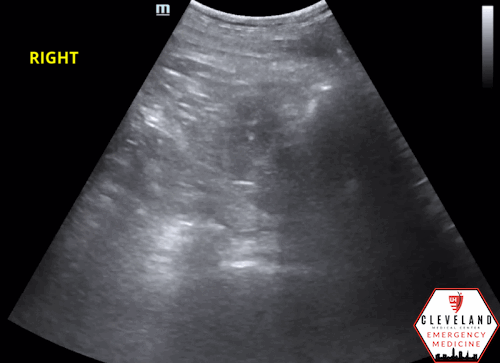

POCUS findings:

Dilated renal pelvis with multiple coalescing, anechoic calyces and parenchymal thinning, consistent with severe hydronephrosis bilaterally — new on the left, with more cortical thinning noted on the right. The bladder (not shown here) was fully decompressed.

**Both of this patient’s kidneys appear to have grade 4 or severe hydronephrosis based on ultrasound.